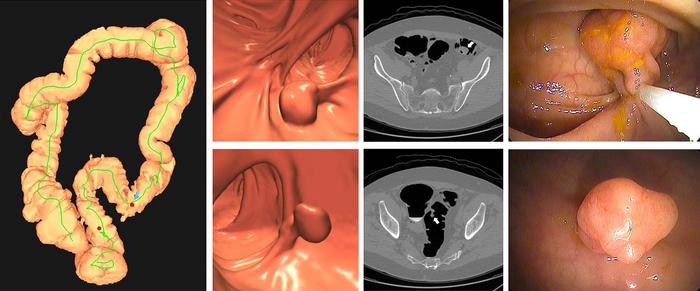

Images of positive CT colonography (CTC) screening examination result in an asymptomatic 67-year-old man. Three-dimensional colon map from CTC (left image) shows the location of two sigmoid polyps that were detected (red dots). Three-dimensional endoluminal and confirmatory two-dimensional transverse CTC images show a large 1.6- cm pedunculated polyp on top row (arrow) and a 9-mm pedunculated polyp in the distal sigmoid on the bottom row (arrow). Both polyps were confirmed and resected at optical colonoscopy performed the same day (right images), avoiding the need for a second bowel preparation. The larger polyp proved to be a tubulovillous adenoma (large advanced adenoma), whereas the smaller polyp was a nonadvanced tubular adenoma. Compare this level of information of a positive CTC screening test result with a positive multitarget stool DNA test result, for which no specific information is provided.